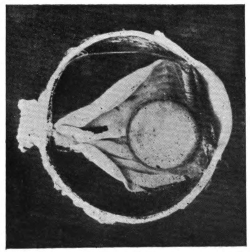

PLATE II.

FACING

PAGE

10.

LENS DISLOCATED BETWEEN CILIARY BODY AND SCLERA

curly bracket span

38

11.

NUCLEUS OF CATARACT FREELY MOVABLE BETWEEN THE AQUEOUS AND VITREOUS CHAMBERS

12.

LENS IMPACTED IN ANGLE OF ANTERIOR CHAMBER

13.

CAPSULE OF MORGAGNIAN CATARACT IMPACTED IN ANGLE OF ANTERIOR CHAMBER

14.

LENS FLOATING FREE IN VITREOUS CHAMBER

15.

LENS LIGHTLY IMPRISONED IN EXUDATE INTO VITREOUS CAVITY